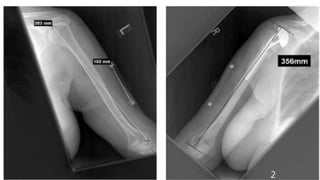

POST OP X-RAY

PATIENT MANAGED WITH MODULAR BIPOLAR CEMENTED HEMIARTHROPLASTY LEFT SHOULDER OTHER TYPE OF HEMIARTHROPLASTY : 1. MODIFIED HEMIARTHROPLASTY: INTERPOSITION ARTHROPLASTY AND GLENOIDPLASTY (REAM AND RUN) 2. RESURFACING HEMIARTHROPLASTY